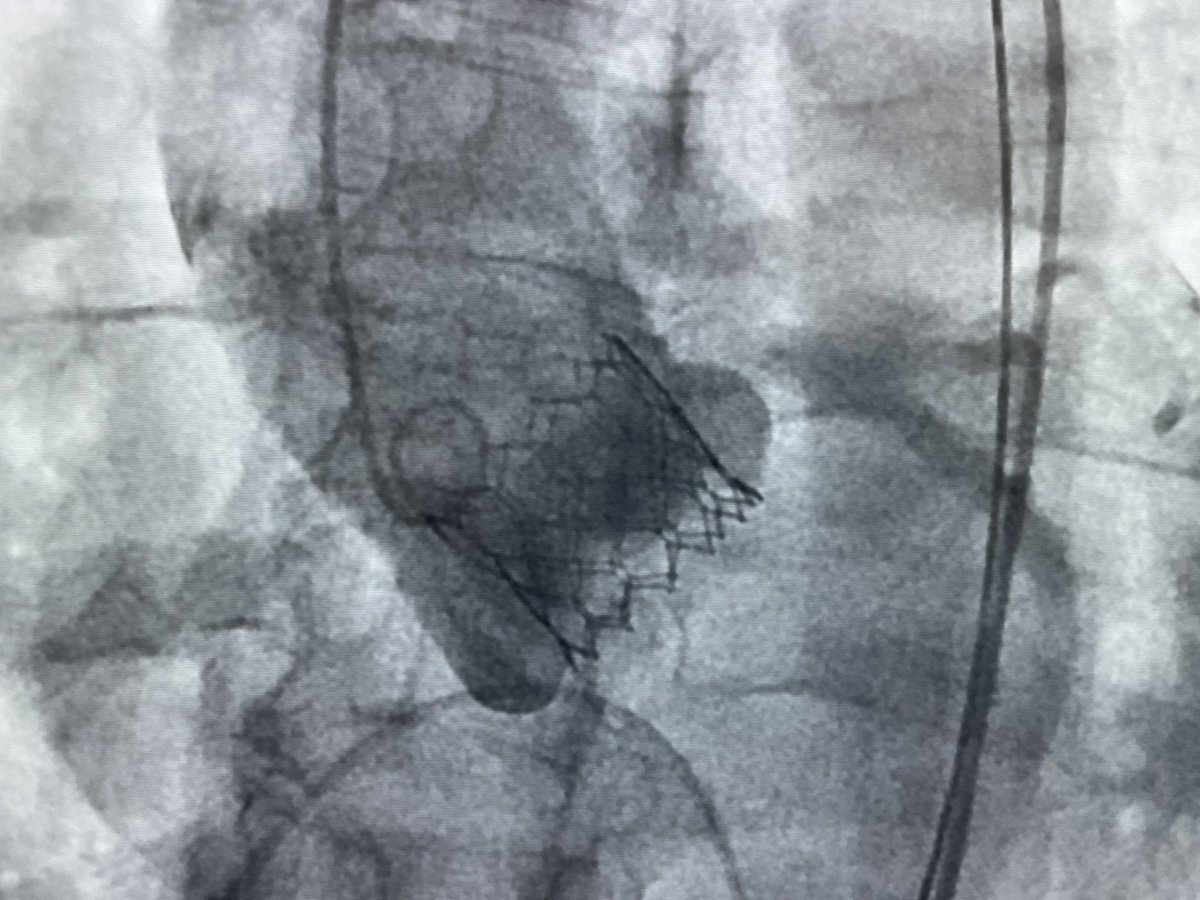

#TAVR of the day with an incredibly tortuous aorta, difficult crossing, but satisfying result. Undersized S3 23mm deployed at nominal with moderate PVL requiring an extra 1ml filling volume. Peak to peak gradient improved from 112mmHg to 0mmHg, no AR. #structuralintervention

YinghaoLim's tweet image. #TAVR of the day with an incredibly tortuous aorta, difficult crossing, but satisfying result. Undersized S3 23mm deployed at nominal with moderate PVL requiring an extra 1ml filling volume. Peak to peak gradient improved from 112mmHg to 0mmHg, no AR.

#structuralintervention